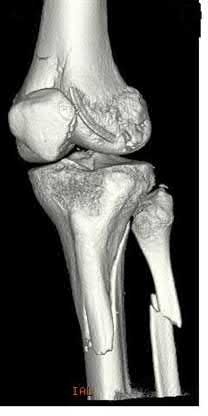

Figures A-C are the radiographs of a 26-year-old male who presents to the emergency department following a motocross accident. Two attempts at a closed reduction by the on-call orthopedic resident were unsuccessful. Figures D and E are the pre-operative axial CT-images that were obtained. The patient undergoes surgical fixation seen in Figure F. Limitations in post-operative dorsiflexion is likely influenced by which of the following?

The rare Bosworth fracture-dislocation is a posterior dislocation of the fibula which becomes entrapped behind the tibia. As demonstrated in this vignette, these injuries are extremely difficult to close reduce secondary to the ridge of the posterolateral distal tibia. The irreducible nature of this injury is a known risk factor for the development of compartment syndrome. The CT images further demonstrate fracture extension to the posteromedial rim (“posterior pilon variant”). In this situation, the only effective method to reduce the fracture is through an open posterolateral approach with the interval between the flexor hallucis longus and the peroneal tendons. This is the same approach that is utilized for fixation of the posterolateral fragment and fibula. Loss of dorsiflexion has been demonstrated following this fracture pattern with posterior fixation. The positioning of the plates in Figure F suggests the

utilization of a posterolateral approach.

Figures A-C: The initial radiographs reveal the posterior subluxation of the talus with associated posterior subluxation of the fibula without significant coronal plane deformity. This deformity should raise the suspicion of a Bosworth fracture-dislocation, especially if closed reduction is not successful. Figures D and E: Axial CT images demonstrating Bosworth fracture-dislocation of the fibula entrapped behind the tibia. Also, note the fracture extension to the posteromedial rim in this posterior pilon variant.

Figure F: Positioning of the plate suggests a posterolateral approach to address both the fibula and posterior malleolus fractures.